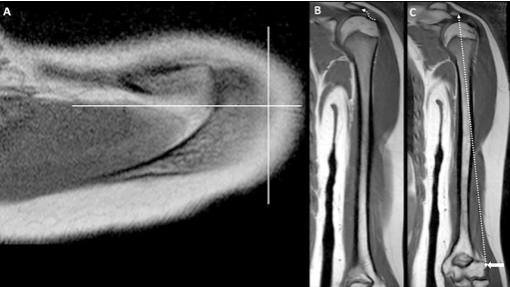

Continue readingEstablecimiento de zonas seguras para evitar lesiones nerviosas en el abordaje del húmero en pacientes pediátricos: un estudio de resonancia magnética.

La anatomía quirúrgica de los nervios periféricos de las extremidades superiores en adultos ha sido bien descrita como «zonas seguras» o distancias específicas de puntos de referencia óseos. En pediatría, las relaciones entre nervios y puntos de referencia óseos siguen siendo ambiguas. El objetivo de nuestro estudio fue desarrollar un modelo para predecir con precisión […]